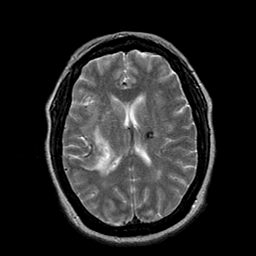

Cerebral hemorrhage, MR Study mr-t2 -- Slice #14

[Home][Help][Clinical] Slice 14